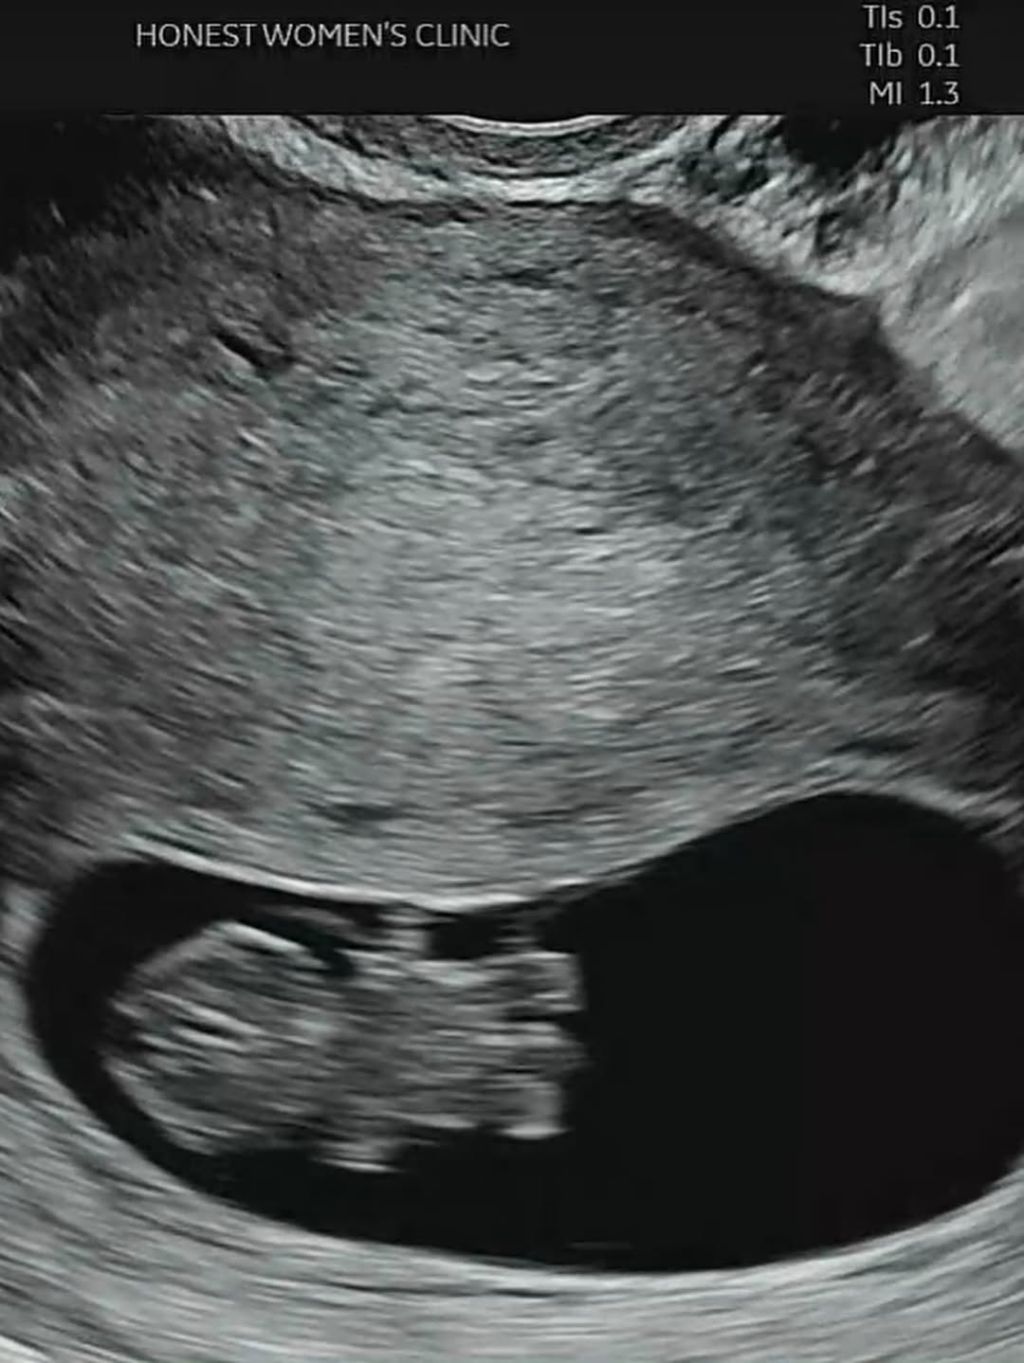

🎈저희 가족에게 새 생명이 찾아왔어여:)

☺️ 제가 곧 엄마가 됩니다 캬캬🍀

• 작성자불침번 | 작성시간 25.12.15 저렇게귀여운초음파사진처음봐 ㅋㅋㅋ